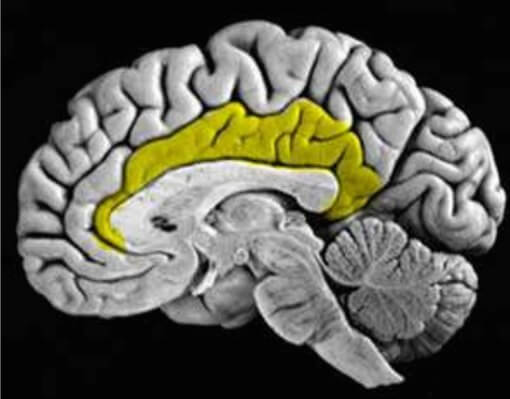

Вчера я рассказал про ручник, который есть у нас мозгу. Поясную извилину можно также сравнить с коробкой переключения передач. При стрессе она заедает, что делает нас негибкими и мы утрачиваем способность приспосабливаться. Такая поведенческая жесткость значительно снижает нашу стрессоустойчивость. Сегодня я расскажу, как нормализовать активность поясной извилины (большинство упражнений из книги Амена "Мозг и любовь").

Все части невральной оси работают сообща, но два ее участка имеют особые механизмы, которые обеспечиваются их нервными отростками, идущими во всех направлениях. Речь идет о передней поясной коре (ППК) и миндалевидном теле.

Начнем с ППК (более полную информацию можно найти в Lewis and Todd, 2007; Paus, 2001). ППК тесно связана с эволюционно молодыми областями префронтальной коры – дорзальной (задней) лобной корой и латеральной (боковой), вместе эту зону обозначают трудно- произносимым термином «дорсолатеральная префронтальная кора (ДЛПК)». Эта зона коры – главный нервный субстрат оперативной памяти ДЛПК – своего рода временное подсобное хранилище, куда мозг выкладывает информацию, требуемую для решения насущной задачи и принятия решений.

По «приказу» ППК множество далеко отстоящих (по микроскопическим масштабам) друг от друга областей начинают пульсировать совместно, координируя фазы всплесков и затуханий, возбуждения и торможения. Обычно эта нейронная синхронность пульсирует в гамма-ритме – от 30 до 80 раз в секунду (Thompson and Varela, 2001). ППК – главный куратор нашего внимания. Она следит за осуществлением нашего продвижения к целям и отмечает противоречия между ними. Ее верхние уровни осуществляют усиленный контроль, преднамеренное и постоянное регулирование мыслей и поведения. Эти области созревают лишь к 3–6 годам (Posner and Rothbart, 2000). В основном именно поэтому дети хуже контролируют себя, чем взрослые. ППК работает каждый раз, когда вы осознанно выполняете свое намерение. Через плотные двусторонние связи с миндалевидным телом, гиппокампом и гипоталамусом ППК влияет на эмоции и сама подвергается их влиянию.